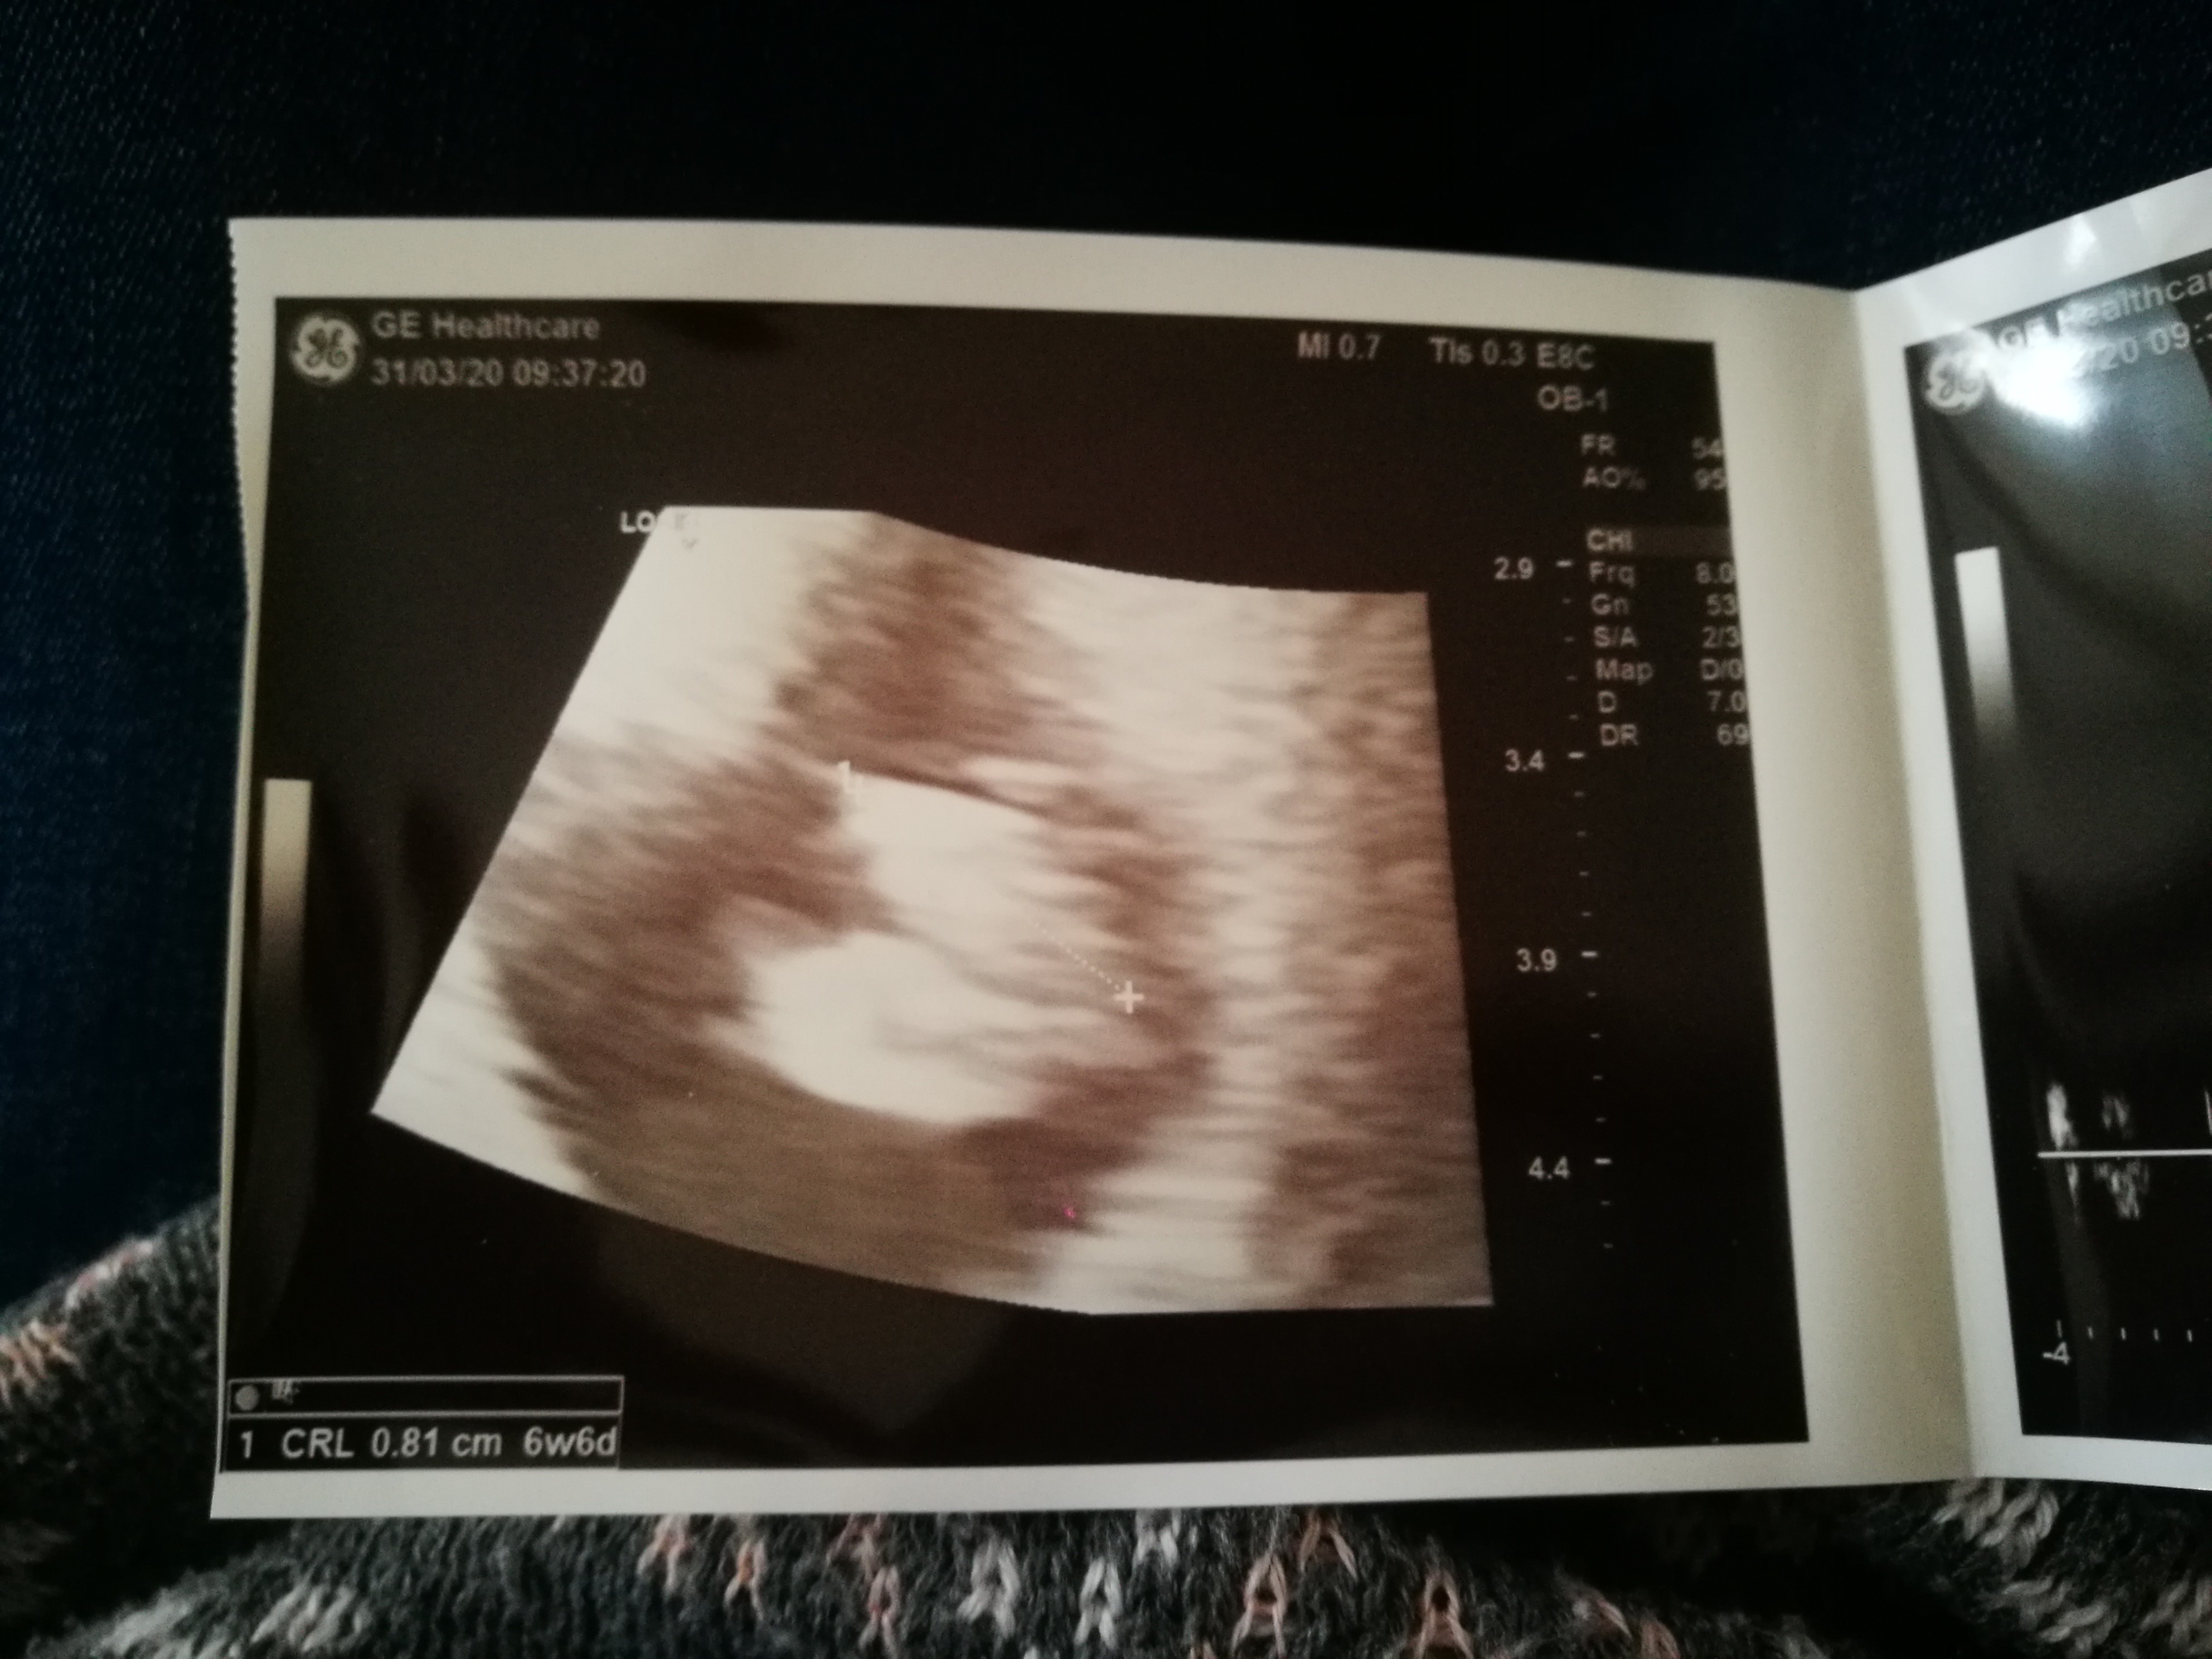

Kochane forumowe ciocie, mam się dobrze, serce mi bije (mama słyszała ;) ) i wczoraj miałam już 8 mm długości :) całuję Was i ściskam mocno. Kropeczka ❤️

Załączniki

• IMG_20200331_155618.jpg

IMG_20200331_155618.jpg

1,2 MB · Wyświetleń: 136

Kochane forumowe ciocie, mam się dobrze, serce mi bije (mama słyszała ;) ) i wczoraj miałam już 8 mm długości :) całuję Was i ściskam mocno. Kropeczka [emoji3590]